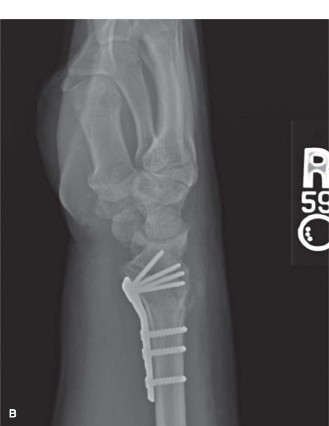

He is taken to the operating room urgently where a carpal tunnel release is performed. He also undergoes ORIF of the distal radius using a volar plate. Postoperative radiographs are shown in Figure 6–27A and B.

Figure 6–27 A–B

Which of the following is true regarding differences in volar and dorsal plating for distal radius fractures?

- The volar fixed angle plates allow for improved fixation of osteopenic bone or those fractures with metaphyseal defects.

The correct answer is (D). While classically the distal radius was approached and plated dorsally, there has been a transition in the recent past to performing a large number of distal radius fracture ORIF procedures through a volar approach. Choice A is incorrect because the radiocarpal joint is visualized more easily from the dorsal approach due to the presence of the volar wrist ligaments. Extensor tendon, as well as flexor tendon, irritation and rupture is seen with both dorsal and volar plating. Lister’s tubercle can be deceiving on the lateral view when performing volar plating, and exposed screw tips dorsally is a risk for tendon irritation. Placing the volar plate too distal on the radius, past the “watershed line,” increases the risk of plate contact with the flexor tendons and subsequent development of irritation and potentially rupture. In addition to the benefit of being able to provide stable fixation to osteopenic bone and fractures with metaphyseal defects, Ruch and Papadonikolakis recently found volar locked plating to have less frequent volar collapse and fewer complications when compared with dorsal plating.